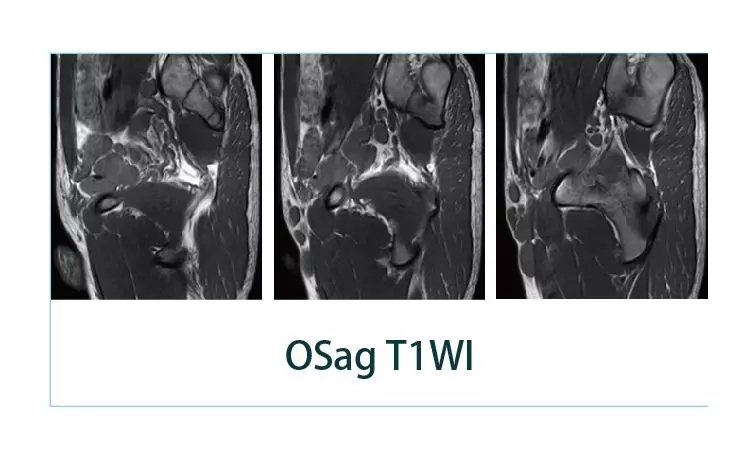

【朗润影像档案】磁共振影像病例分享(编号20190405)